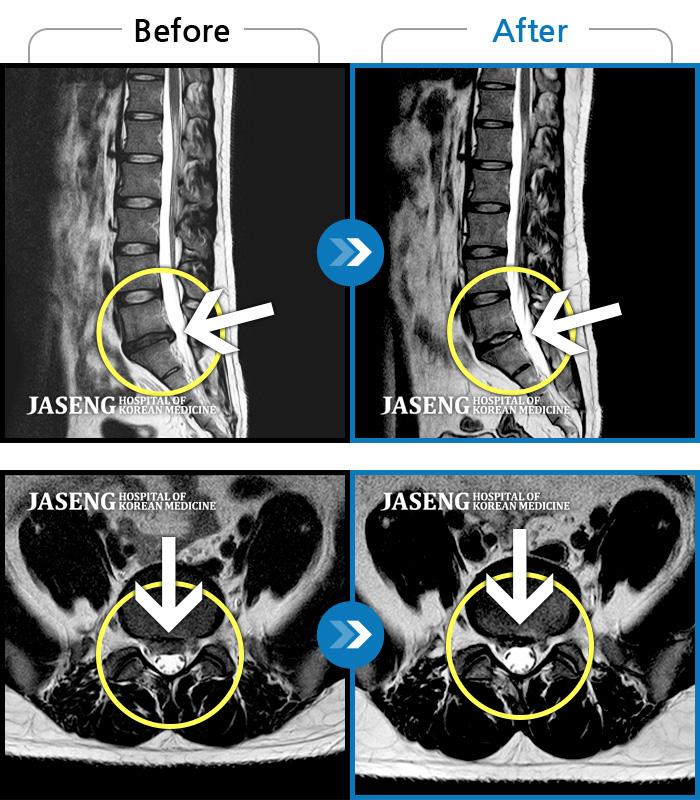

Before

After

환자에게 사전 동의를 받아 동일 조건에서 촬영되었습니다.

개인에 따라 치료 후 부작용이 발생할 수 있으니 의료진과 상담 후 치료를 진행하시기 바랍니다.

처음 내원 시 우측 엉덩이가 많이 아프고, 우측 다리로 근력 및 감각 저하도 있어 발목 움직임이 원활치 못했으며, 야간통으로 잠도 못 자고 통증 심하여 정상적인 활동이 힘든 상태셨습니다.

통증 및 우측 엉치 우측 종아리 땡기는 통증이 심하여 일상생활이 안되는 상태로 내원하셨던 분입니다.